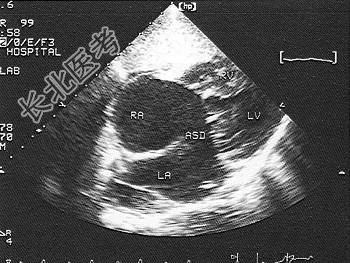

- 单项选择题此图表明为   (   )

A、心内膜垫缺损完全型

B、心内膜垫缺损部分型

C、二尖瓣,三尖瓣关闭不全

D、I孔型房间隔缺损

E、上腔型房间隔缺损